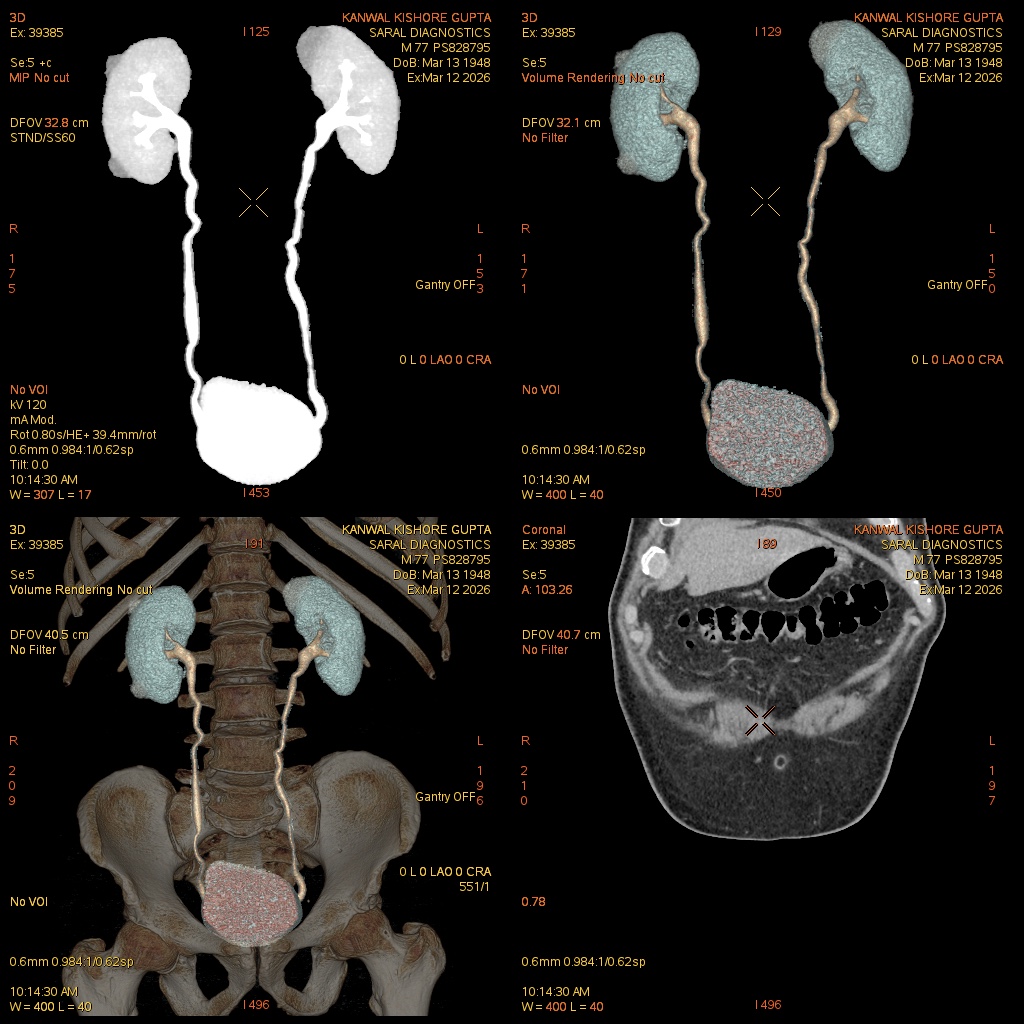

Reference Image

Urography With Contrast